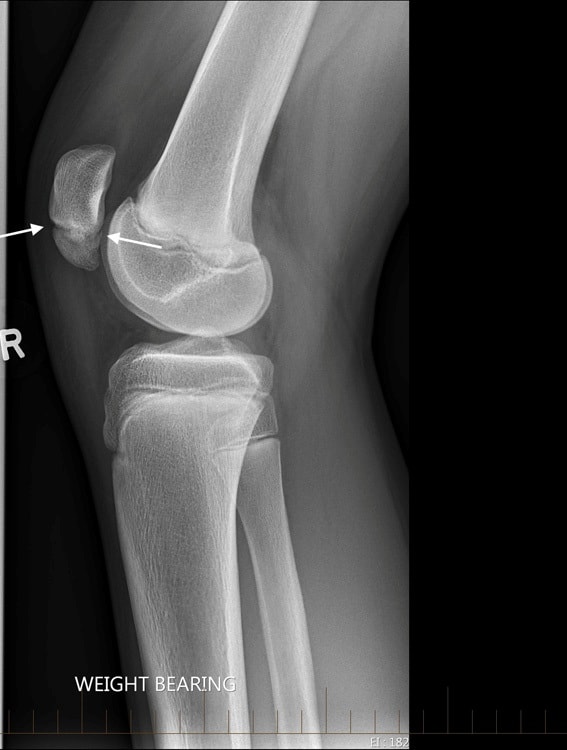

Xương bánh chè 2 mảnh

» Thông tin: Nam giới – 14 tuổi.

» Lâm sàng: Đau khớp gối.